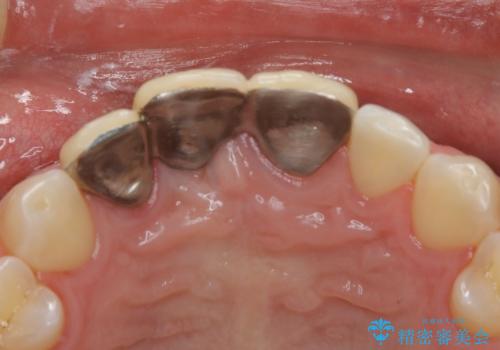

- 前歯ブリッジのやり変えを希望され来院された患者様です。

審美性を重視されていたので、オールセラミッククラウン(スペシャル)でのブリッジを選択されました。